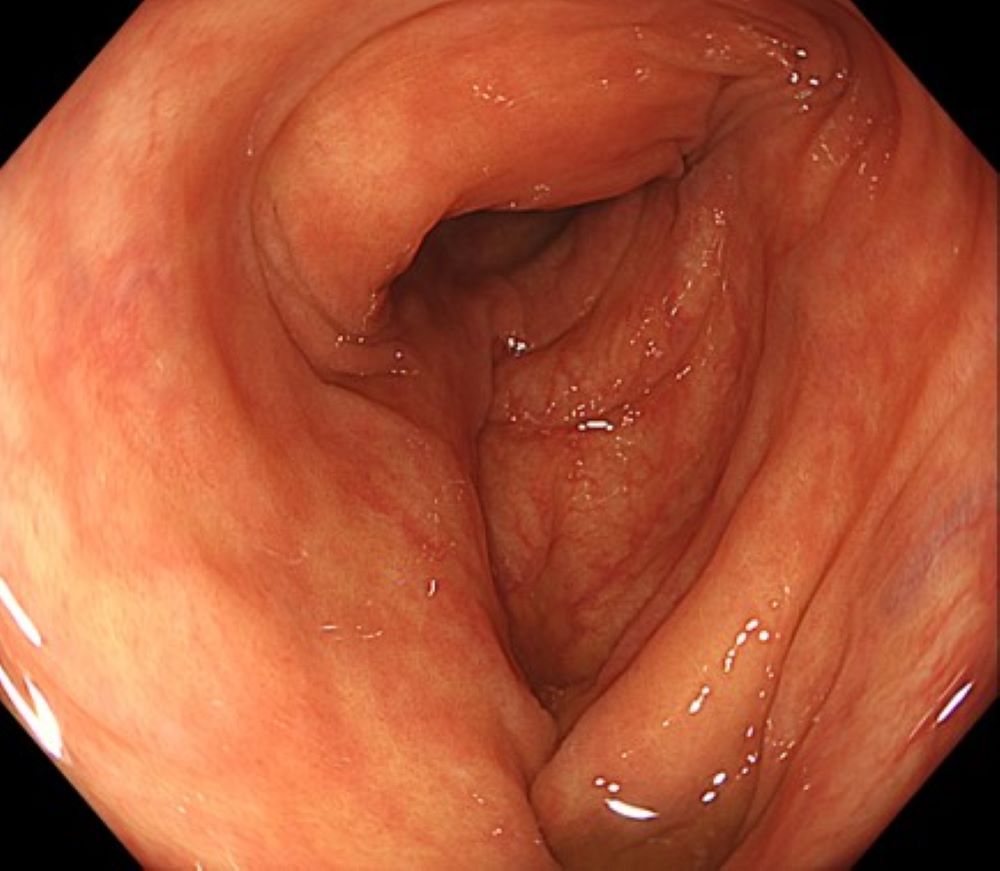

体位変換は、簡便でありながら見落とし防止に有効な手段である。体位を変えることで腸管内の空気や残液の分布が変化し、これまで死角となっていた部位が観察可能となる。特に上行結腸や下行結腸では、半側臥位でも視野の改善が期待できる(※Figure4)。

• ※Figure 4. 下行結腸の観察(体位変換)

(a) 通常の送気量で観察するが管腔は伸展しない

•

(b)通常の送気量のまま半右側臥位ですることで管腔が伸展する